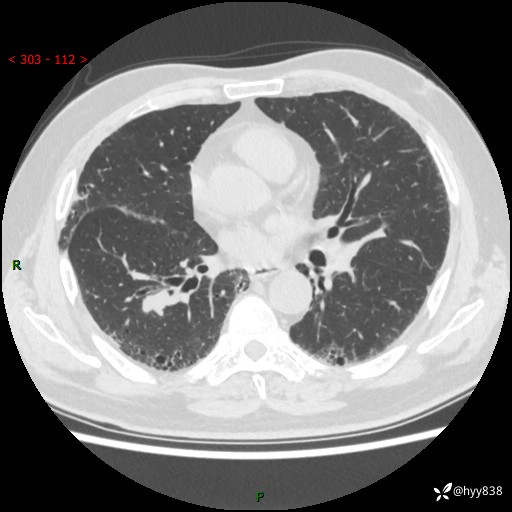

71岁/男,咳嗽伴气促半月。一年前肺手术史,又见两个结节,穿刺结果意外---结果公布~

【现病史】:患者半月前无明显诱因出现咳嗽、咳痰,为白色粘痰,无明显加重与缓解因素,伴气促,无发热,无大量脓痰,无胸痛、咯血,无哮鸣音,到我院就诊,胸部CT示右肺结节增大,并口服药物治疗无明显好转,具体用药不详,为求进一步治疗随来我院,经门诊以“孤立性肺结节”收入我科。 病程中患者精神、饮食可,睡眠不佳,大小便正常,体力下降,体重未见明显下降。

[既往史]:2022-06于当地第一人民医院确诊慢阻肺,现规律使用杰润(1次/日);2023-04-06于当地市第一人民医院行胸腔镜右肺上叶楔形切除术+右肺上叶切除术+淋巴结清扫术+胸膜黏连松解术,确诊为右肺鳞癌 pT2aN0M0 Ib期

【检查】:胸部CT平扫+增强